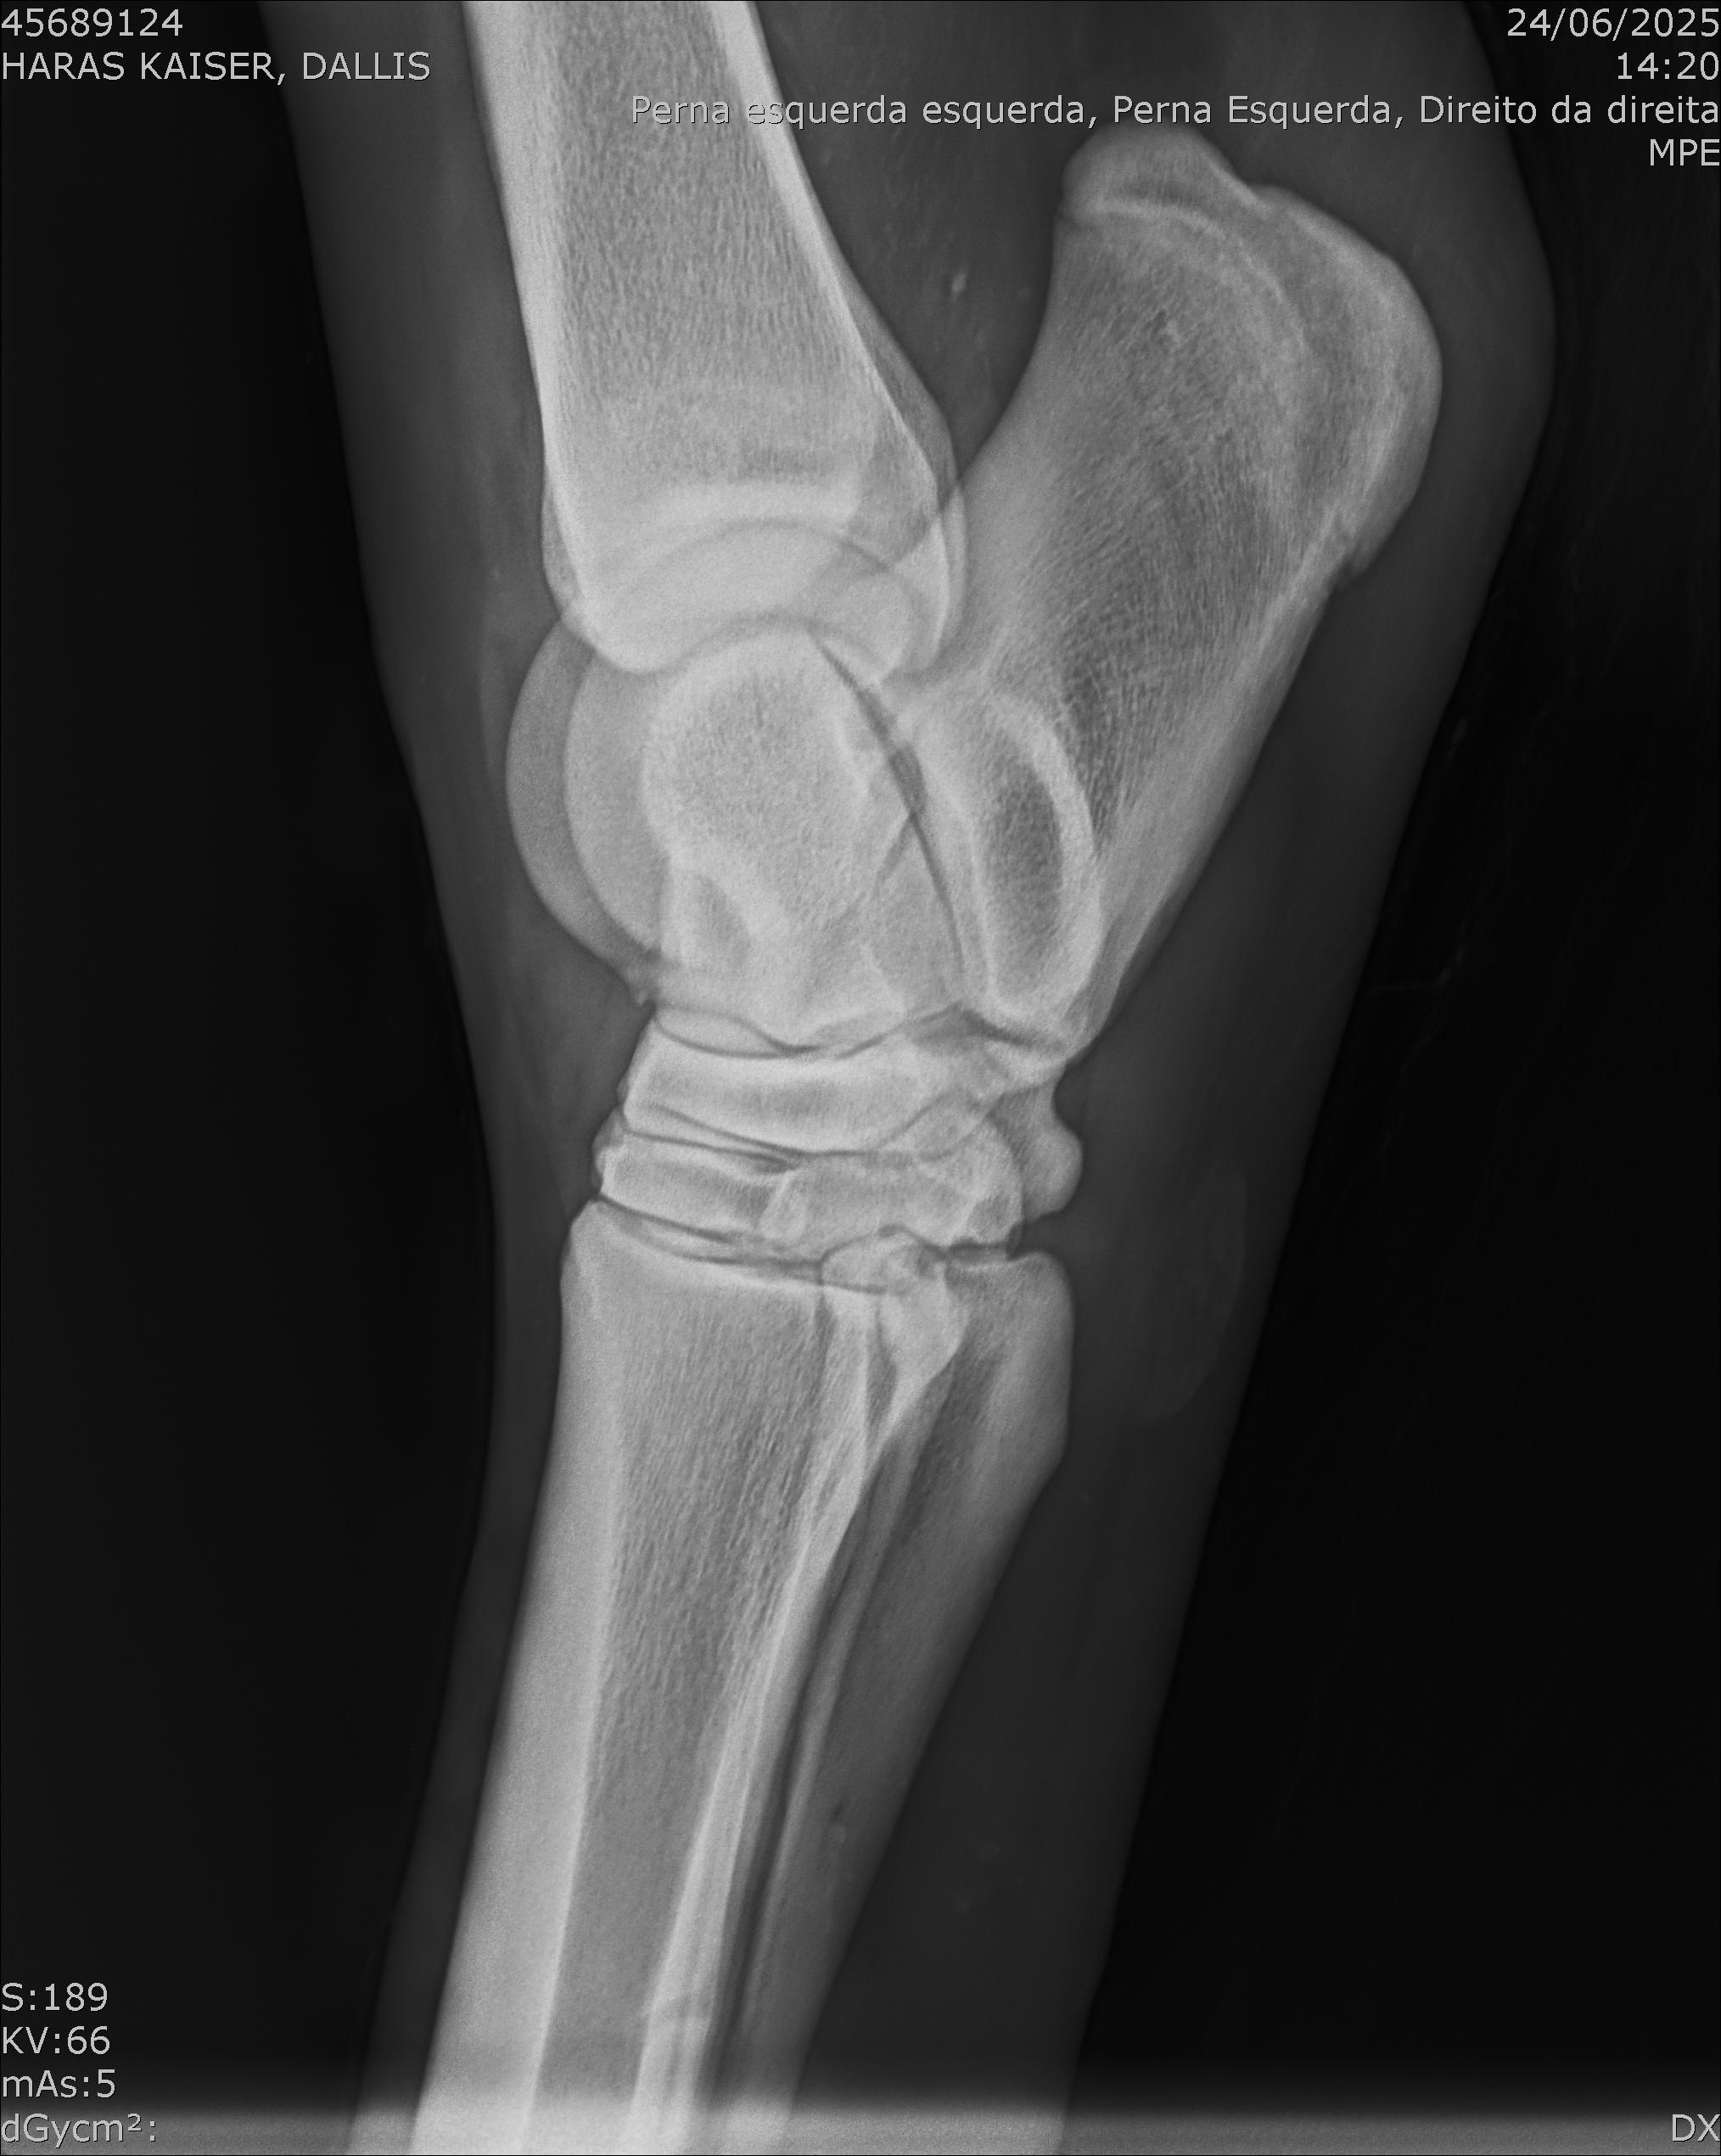

:: RAIOS-X DO LOTE